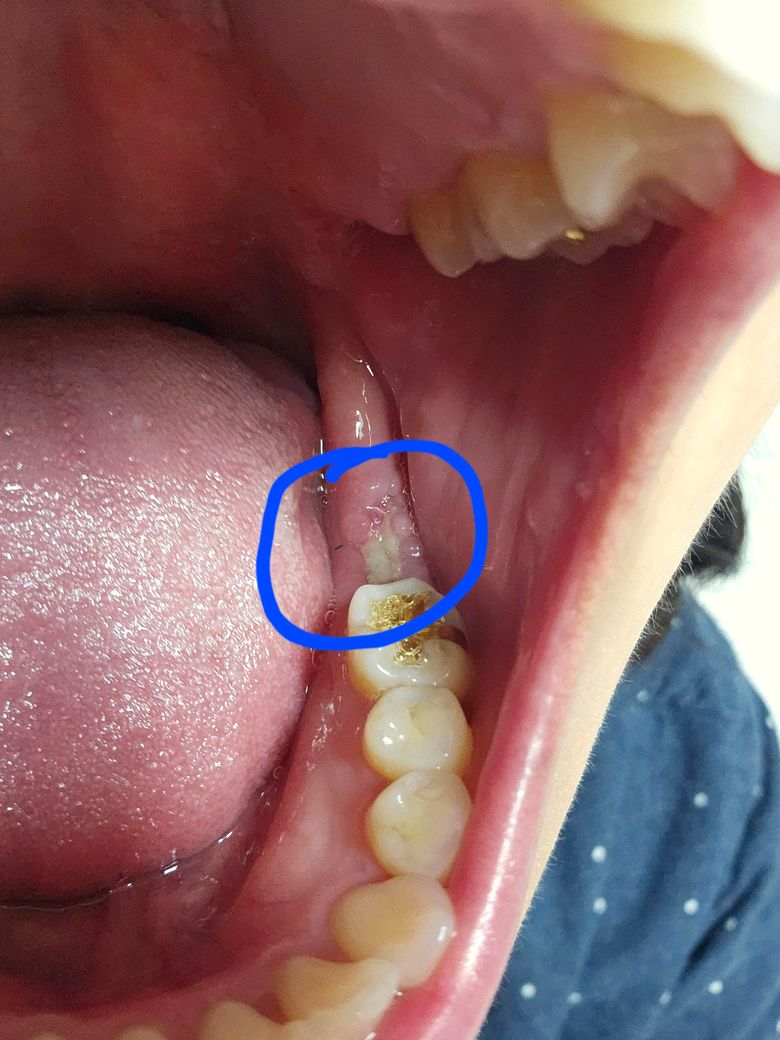

임플란트 뼈이식 후 실밥 풀었는데.. 멍도 안빠지고 실밥이 남아 있는 것 같아요. 실밥제거는 추가로 되는거겠죠?

2주 전에 어금니 발치, 뼈이식 했어요. 실밥 풀고 와서 저녁에 양치하고 보니 뭐가 있는 것 같아서 사진 찍었는데.. 저거 실밥아닐까요? 실밥처럼 보여서 너무 찜찜하더라고요.. 오늘은 보니 잇몸에 파묻힌 느낌도 있어요. 병원에 가서 이정도 실밥은 마저 제거 가능할까요?

그리고 잇몸에서 하얗게 되는 부분은 낫고 있는 걸까요? 병원에서는 괜찮다고 하는데 이따금씩 쿡 찌르는 듯이 턱도 아픈 느낌이 있어 걱정이 됩니다ㅠㅠ

• 1번 째 사진

사진으로만 봤을 경우에는 실밥일 가능성이 높아 보입니다. 잇몸이 붓게 되면 실밥이 잇몸 안에 묻혀 있게 되어 남아있는 경우도 있습니다. 실밥인 경우에는 제거를 해주는 것이 좋을 수 있으니. 치과에서 진료를 받아보는 것이 좋습니다.

잔여 실밥 가능성이 있을 것 같습니다. 치과가서 다시 한번 봐달라고 하세요. 잇몸은 다소 염증 양상이나 위생관리 잘해주면 잘 나을 겁니다. 너무 걱정마세요